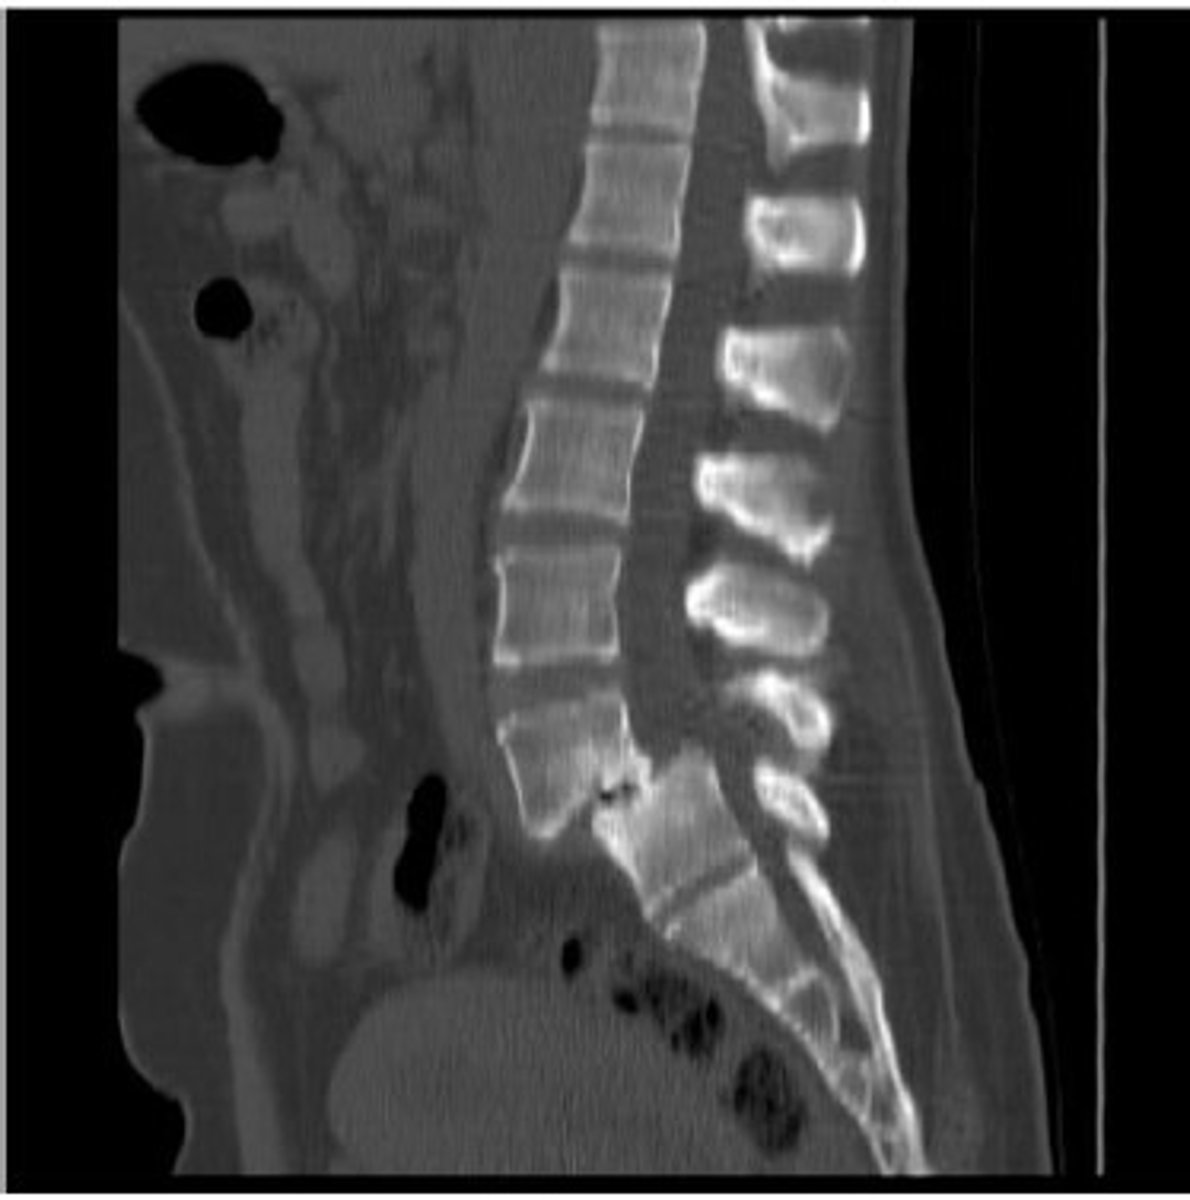

During the examination, the patient reports increased

pain while standing. Pain is alleviated with lumbar

flexion and sitting. Which special test will be positive to

confirm the diagnosis shown in the picture ?

A. Stork standing test

B. Gillet Test

C. Van Gelderen bicycle test

D. Quadrant Test

Spondylolisthesis

Answer: A. Stork standing test

B. Gillet test - SI clusters

C. Van Gelderen bicycle test - spinal stenosis

Spondylolisthesis vs Stenosis:

• Fracture Ant (Antero-listheis)/Retrolisthesis

• X-ray view (Lateral)

• B lateral fracture pars interarticularis

• Contraindication ex’s Extension (No extension)